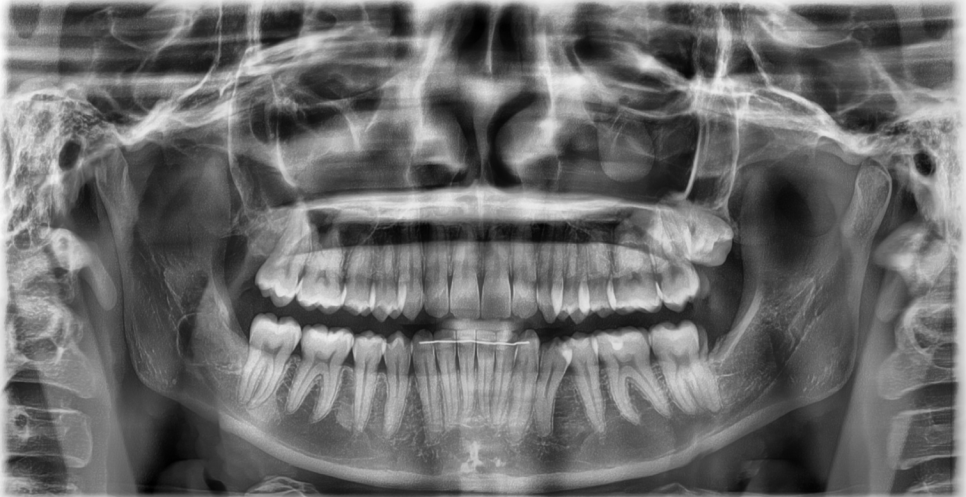

특히 매복 사랑니,

혹은 비스듬히 누워 있는 사랑니라면

앞쪽 어금니까지 영향을 주는 경우도 많습니다.

이 경우

사랑니 하나 문제가 아니라

멀쩡하던 어금니 치료까지 이어질 수 있습니다.

실제 치아 상태,

잇몸 속 위치,

신경과의 거리,

웃거나 씹을 때 사용하는 범위까지

직접 확인해야 정확한 판단이 가능합니다.